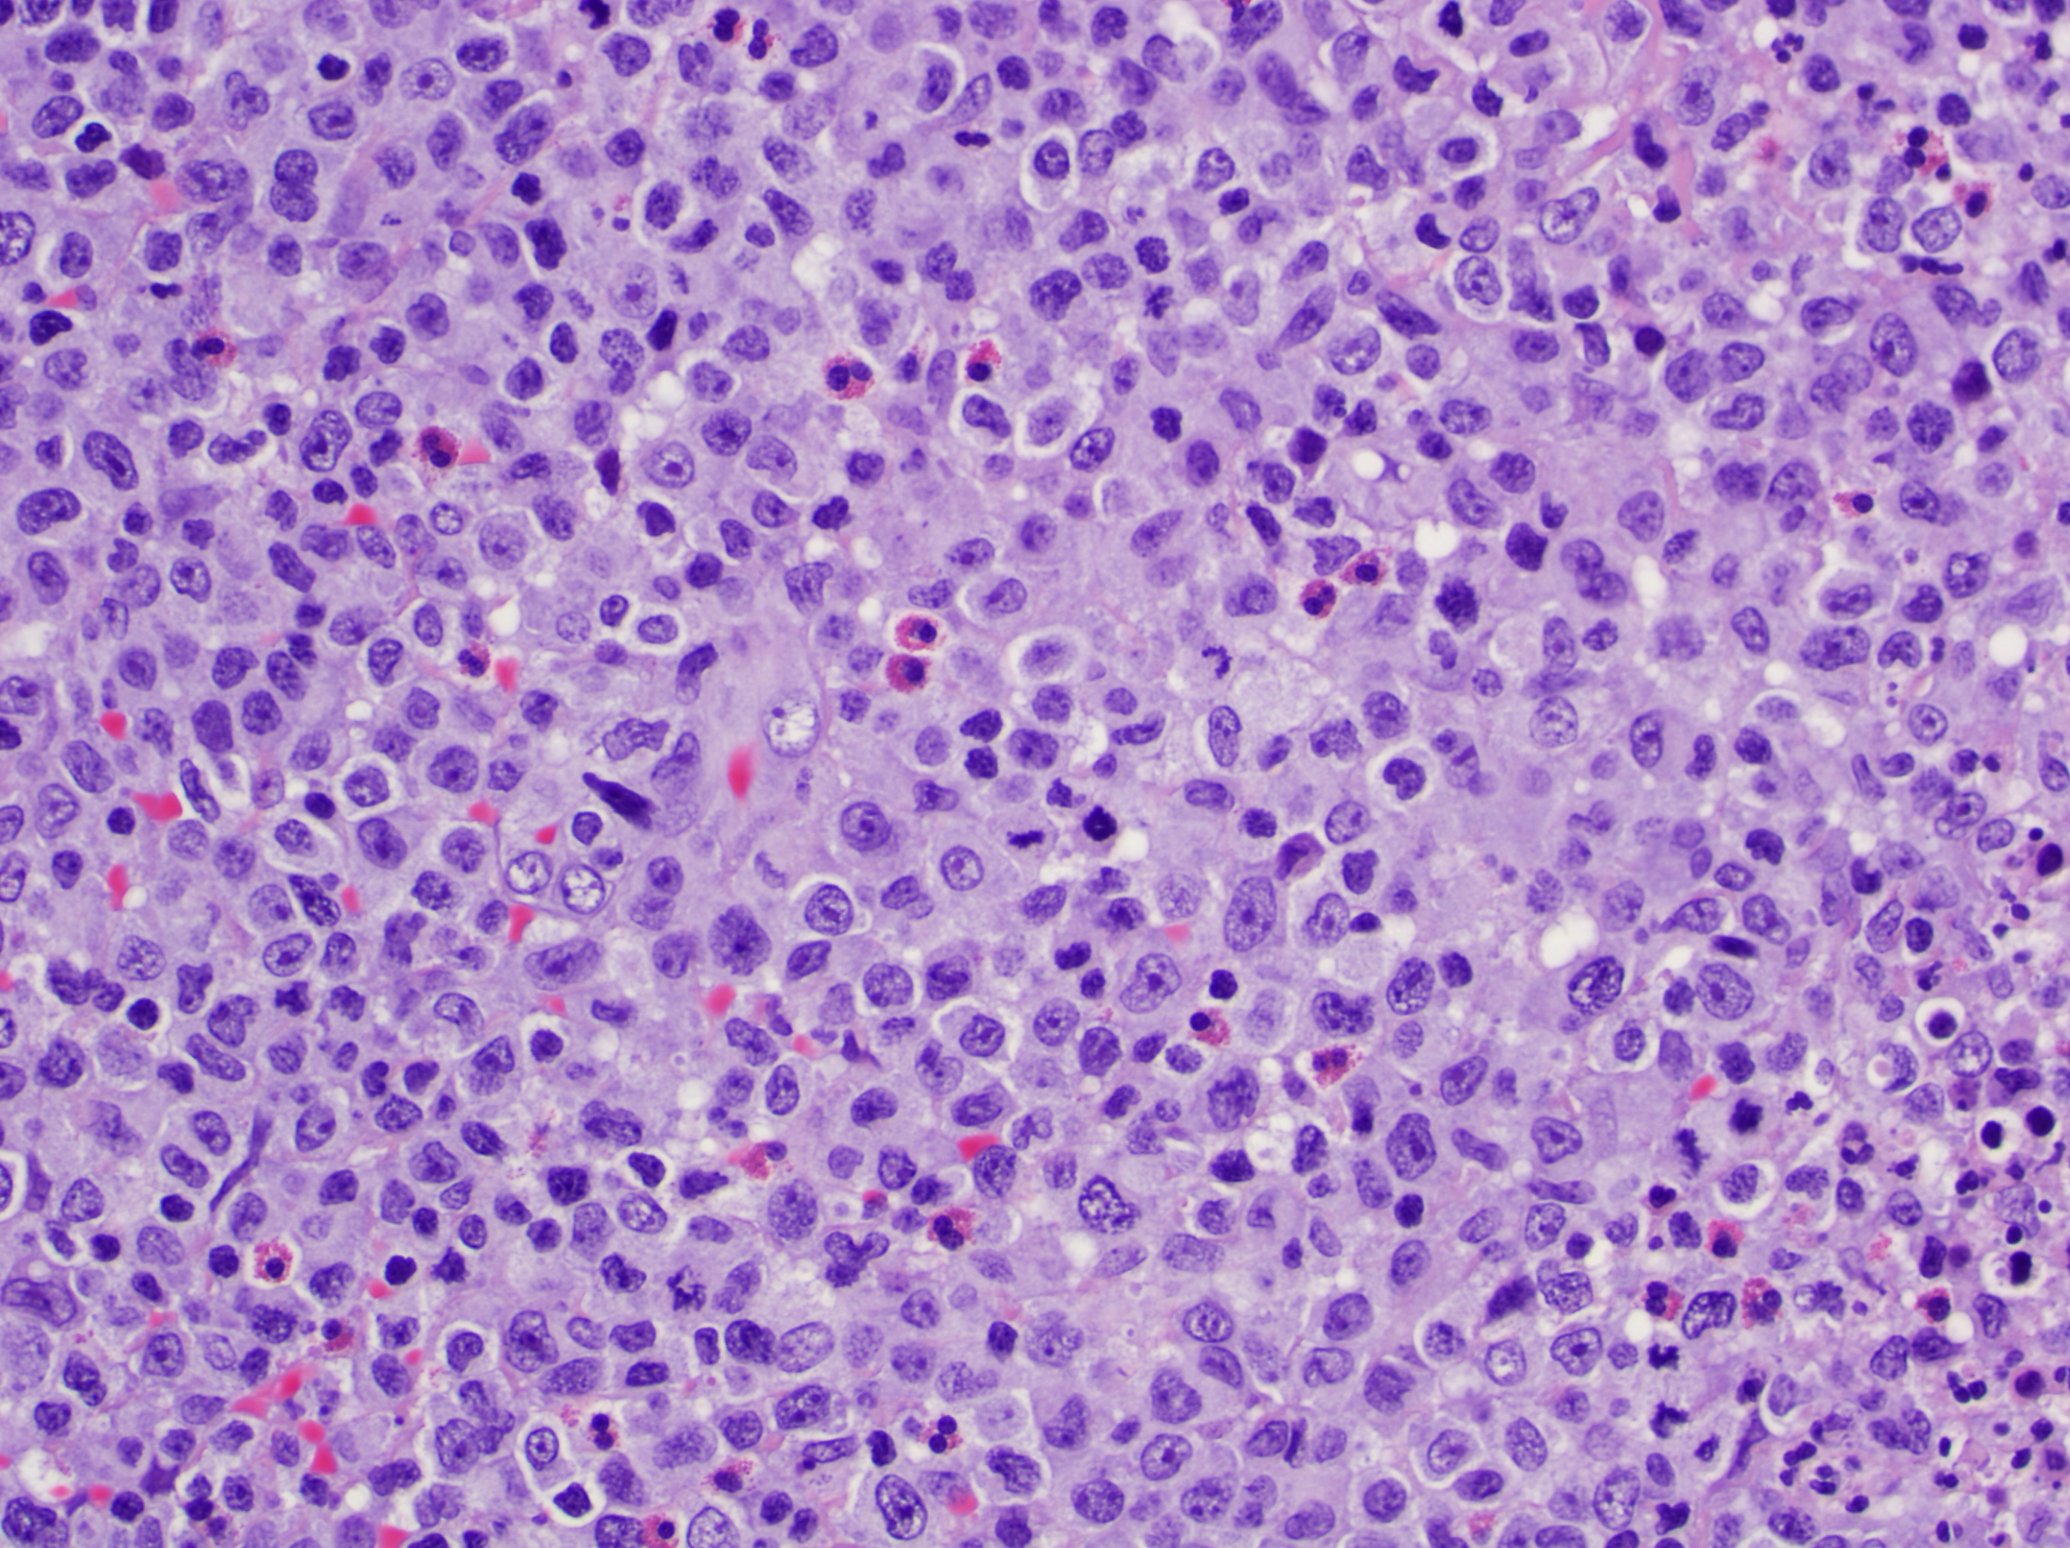

Microscopic (histologic) description

- Lymphomatoid papulosis is characterized by a wedge shaped pattern, with a wide superficial base and the tip at the bottom, usually deep dermis and less frequently into the subcutaneous tissue

- The most characteristic appearance is the presence of few to numerous large cells with a Hodgkin or Hodgkin-Reed Sternberg admixed with a reactive background of small lymphocytes and less frequently eosinophils, plasma cells and histiocytes

- The microscopic appearance and immunophenotype of large cells is variable and led to subclassification of lymphomatoid papulosis into different categories (J Am Acad Dermatol 2016;74:59, Blood 2019;133:1703, Semin Diagn Pathol 2017;34:22, J Am Acad Dermatol 2013;68:809, J Am Acad Dermatol 2012;66:928, Am J Clin Pathol 2003;119:731, Am J Surg Pathol 2010;34:1168, Am J Surg Pathol 2013;37:1)

- Type A: wedge shaped and extensive lymphoid infiltrate with neutrophils, eosinophils and histiocytes; CD30+ cells are scattered and the overall histologic appearance mimics classic Hodgkin lymphoma

- Type C: sheets of large cells, uniformly positive for CD30, with or without epidermotropism and few admixed inflammatory cells; the lesion mimics primary cutaneous anaplastic large cell lymphoma

Microscopic (histologic) images

Contributed by Roberto N. Miranda, M.D.